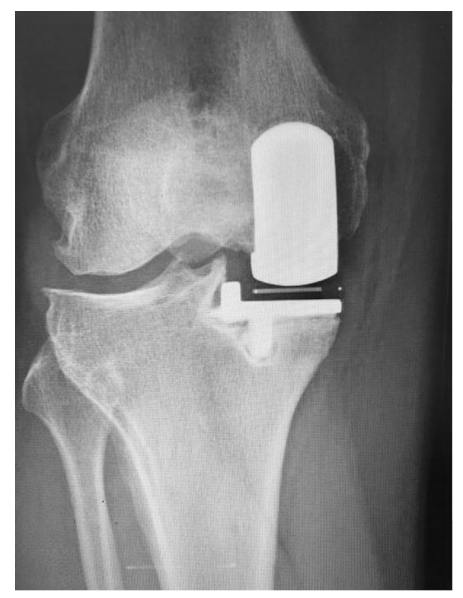

Kozinn和Soctt的经典限制性纳入标准在现代研究中得到了极大的扩展,这些研究表明UKA在年轻患者、肥胖患者、髌股疾病患者以及那些非常活跃的患者中取得了成功。无论如何,正确的患者选择对于确保UKA的成功结果仍然至关重要。对于所有前内侧OA(图1)、畸形可纠正(图2)、膝关节韧带完好、膝关节活动范围保留、屈曲挛缩小的患者,都可以考虑内侧UKA。

图1:计算机断层扫描显示前内侧骨关节炎。